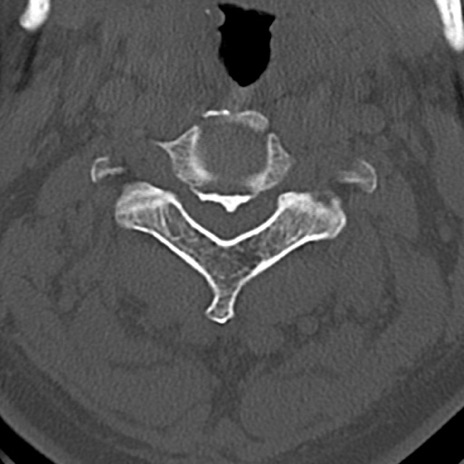

頚椎CT

横断像